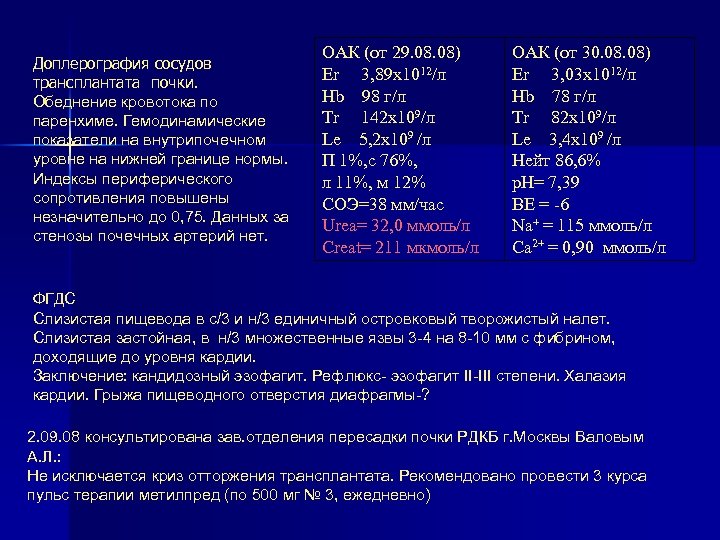

Доплерография сосудов трансплантата почки. Обеднение кровотока по паренхиме. Гемодинамические показатели на внутрипочечном уровне на нижней границе нормы. Индексы периферического сопротивления повышены незначительно до 0, 75. Данных за стенозы почечных артерий нет. ОАК (от 29. 08) Er 3, 89 х1012/л Hb 98 г/л Tr 142 х109/л Le 5, 2 х109 /л П 1%, с 76%, л 11%, м 12% СОЭ=38 мм/час Urea= 32, 0 ммоль/л Creat= 211 мкмоль/л ОАК (от 30. 08) Er 3, 03 х1012/л Hb 78 г/л Tr 82 х109/л Le 3, 4 х109 /л Нейт 86, 6% p. H= 7, 39 ВЕ = -6 Na+ = 115 ммоль/л Ca 2+ = 0, 90 ммоль/л ФГДС Слизистая пищевода в с/3 и н/3 единичный островковый творожистый налет. Слизистая застойная, в н/3 множественные язвы 3 -4 на 8 -10 мм с фибрином, доходящие до уровня кардии. Заключение: кандидозный эзофагит. Рефлюкс- эзофагит II-III степени. Халазия кардии. Грыжа пищеводного отверстия диафрагмы-? 2. 09. 08 консультирована зав. отделения пересадки почки РДКБ г. Москвы Валовым А. Л. : Не исключается криз отторжения трансплантата. Рекомендовано провести 3 курса пульс терапии метилпред (по 500 мг № 3, ежедневно)

Доплерография сосудов трансплантата почки. Обеднение кровотока по паренхиме. Гемодинамические показатели на внутрипочечном уровне на нижней границе нормы. Индексы периферического сопротивления повышены незначительно до 0, 75. Данных за стенозы почечных артерий нет. ОАК (от 29. 08) Er 3, 89 х1012/л Hb 98 г/л Tr 142 х109/л Le 5, 2 х109 /л П 1%, с 76%, л 11%, м 12% СОЭ=38 мм/час Urea= 32, 0 ммоль/л Creat= 211 мкмоль/л ОАК (от 30. 08) Er 3, 03 х1012/л Hb 78 г/л Tr 82 х109/л Le 3, 4 х109 /л Нейт 86, 6% p. H= 7, 39 ВЕ = -6 Na+ = 115 ммоль/л Ca 2+ = 0, 90 ммоль/л ФГДС Слизистая пищевода в с/3 и н/3 единичный островковый творожистый налет. Слизистая застойная, в н/3 множественные язвы 3 -4 на 8 -10 мм с фибрином, доходящие до уровня кардии. Заключение: кандидозный эзофагит. Рефлюкс- эзофагит II-III степени. Халазия кардии. Грыжа пищеводного отверстия диафрагмы-? 2. 09. 08 консультирована зав. отделения пересадки почки РДКБ г. Москвы Валовым А. Л. : Не исключается криз отторжения трансплантата. Рекомендовано провести 3 курса пульс терапии метилпред (по 500 мг № 3, ежедневно)